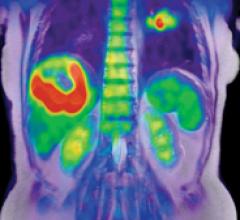

The addition of magnetic resonance (MR) imaging and spectroscopy to positron emission tomography (PET) is more expensive and more technically challenging compared with PET/computed tomography (CT). PET/CT is successful because the inclusion of CT has major advantages: accurate lesion localization, the identification of non-PET avid lesions and effective attenuation correction in a rapid, efficient combined examination. The addition of CT is particularly valuable for lungs and liver, where fluorodeoxyglucose (FDG) PET is limited by spatial resolution and relatively low target-to-background differential biodistribution. Presumably, PET/MR may disclose unique important diagnostic and prognostic information in selected patient groups.

Researchers from University Hospitals Case Medical Center have published findings that a new form of imaging — magnetic resonance imaging/ positron emission tomography (PET/MRI) — is promising for several types of cancer.